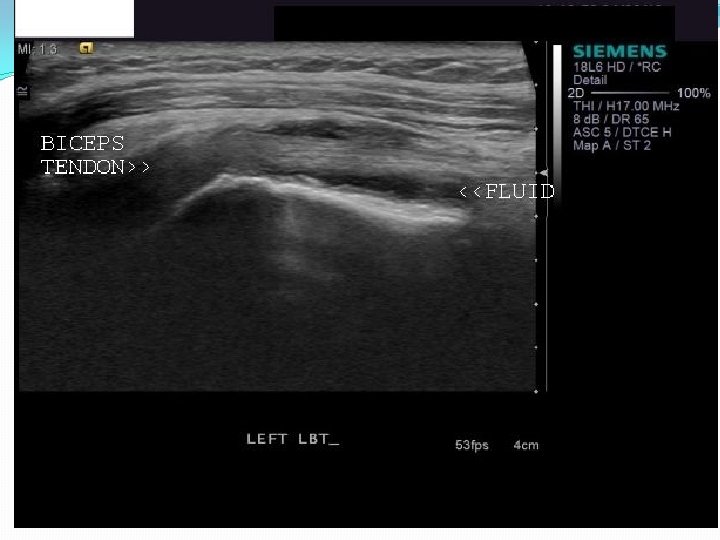

Sonography of Patients with Hemiplegic shoulder pain after stroke Lee et al Am J Roentgen 2009 Feb; 192(2): �n=71, 20 pts had bilateral shoulders scanned �Subacromial bursal effusion seen in 36 shoulders �Biceps tendon sheath effusion in 39 shoulders �Supraspinatus tendinosis (7), partial tear (6) and full tear (2) �Abnormalities more common in hemiplegic shoulder p=. 007 vs uninvolved side

Case study Mr. H �Ultrasound R shoulder- 3 mm fluid surrounding the R biceps tendon in the groove on SAX/LAX views, no cuff abnormalities, AC joint ok �R biceps tendon sheath injection under ultrasound guidance �Resolution of R shoulder pain �Completed outpatient PT/OT- no recurrence �Still gets botox injections to forearm and biceps q 3 months

HSP Summary �New tools such as MSK ultrasound may improve accuracy of HSP diagnosis �Bicipital tendinopathy/tenosynovitis more common than previously thought �Subscapularis tear more common than previously thought in chronic stage �Improved diagnosis can improve treatment